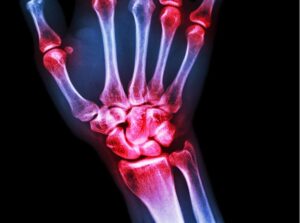

כאב במפרק האגודל

. אם יש לך כאב במפרק האגודל, יש כמה דברים שיכולים לגרום לזה

דלקת מפרקים באגודל יכולה להיות קשורה לאוסטאוארתריטיס

(המשפיעה על המפרק והעצם) או דלקת מפרקים שגרונית (מצב אוטו-אימוני).

כאב במפרק האגודל שנגרם על ידי דלקת פרקים

יכול להרגיש כמו צריבה, דקירה או כאב חריקה עדין יותר.

כאב במפרק האגודל יכול להיות סימפטום של תסמונת התעלה הקרפלית

בתסמונת התעלה הקרפלית יכולות להיות תחושות חולשה,

חוסר תחושה, עקצוץ או צריבה בפרק כף היד, באצבעות או במפרקי הידיים.

כאב במפרק האגודל יכול להיות סימפטום

של פגיעה באגודל או שימוש יתר או דלקת מפרקים בסיסית.

כאבי מפרקים באצבעות

כאשר אתה מרגיש כאבי מפרקים באצבעות או עקצוץ וחוסר תחושה,

יכול גם להיות שהאצבעות יהיו נוקשות

ויהיה חוסר יכולת להזיז את האצבעות בחופשיות.

חלק מהאנשים עם דלקת מפרקים פסוריאטית עלולים לחוות שינוי במראה הציפורניים שלהם.

כאשר יש נזק לסחוס במפרקי האצבעות, אדם עלול לשמוע רעשי צריבה או שחיקה. זה ידוע בשם קרפיטוס.

הסימנים האלו של כאבי מפרקים באצבעות או חלק אחר

מהסימפטומים כאן לעיל מעידים על דלקת של כאבי מפרקים באצבעות הידיים.